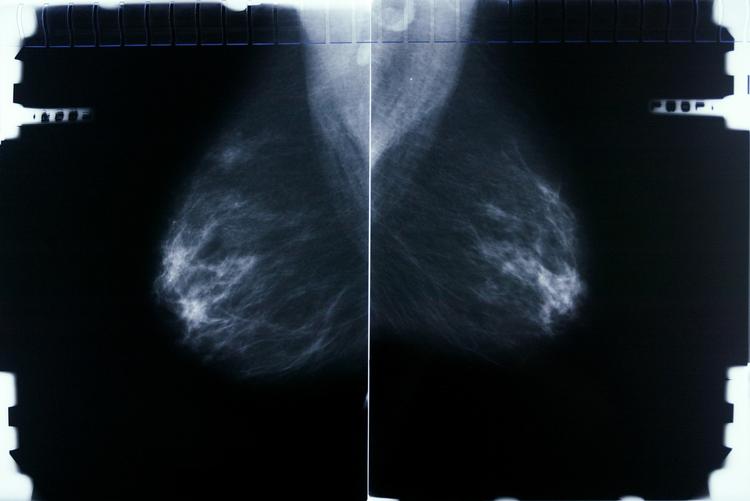

Der sad jeg så søndag morgen sammen med andre kvinder på 50-69 år og ventede på at blive kaldt ind til mammografiscreening. Da jeg kort forinden var cyklet ad den lysegrønne allé på Bispebjerg Hospital, tænkte jeg, at jeg bor i et fantastisk land, der tager vare på befolkningen.

Ventetiden var kort, men lang nok til at sende en tanke til de kvinder i min omgangskreds, der har fået konstateret brystkræft inden for de sidste få år. Selv om jeg ikke selv havde mistanke om kræft, nåede jeg lige akkurat at blive bekymret, inden det blev min tur. 1 ud af 9 kvinder får brystkræft.